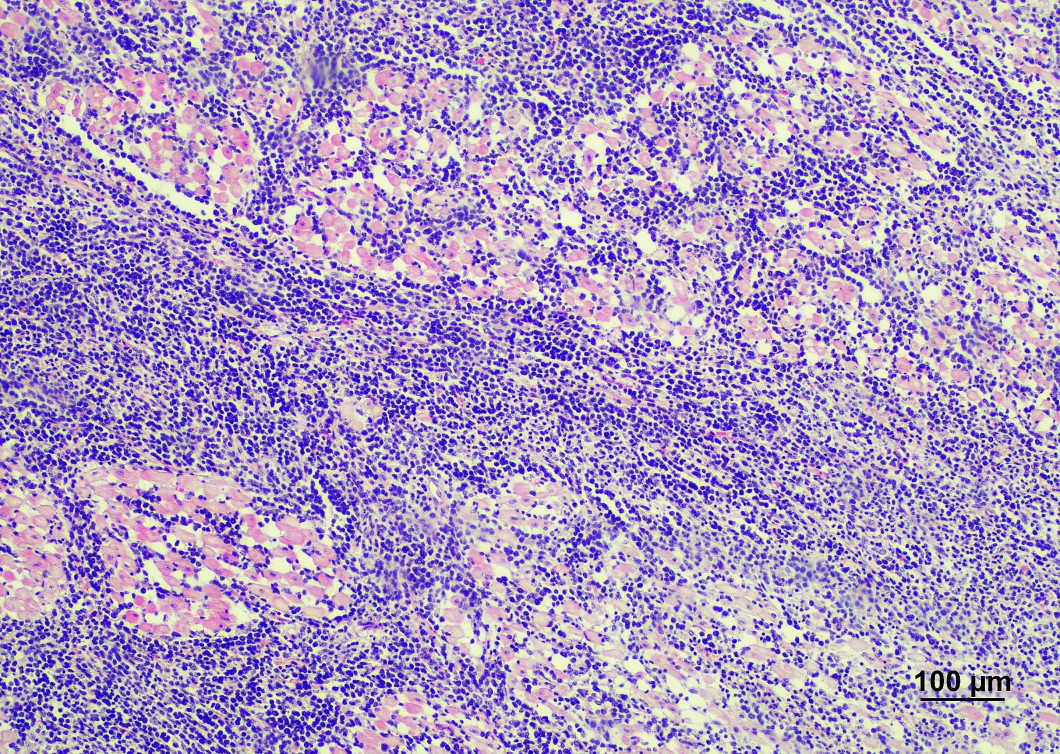

豚の膿毒症から分離されたTrueperella pyogenes

病理組織学的検査

血液や臓器の細胞や組織を顕微鏡で観察し、疾病の診断を行います。

牛伝染性リンパ腫 心臓の白色腫瘤のヘマトキシリン・エオジン染色(心筋に異型リンパ球が浸潤)